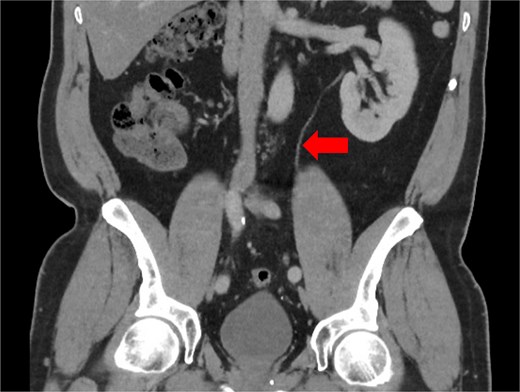

Duplicated ureters originate from two non-communicating pyelocaliceal systems, draining into the urinary bladder either at a single ureteric orifice (bifid ureter, incomplete duplication) or by two separate ureteric orifices (double ureter, complete duplication) [3]. This variant occurs due to the formation of multiple or divided ureteric buds from the same mesonephric duct during development [3]. Most cases are found incidentally through imaging such as computed tomography (CT) urograms or intravenous pyelograms [4], through post-mortem studies [3], or occasionally intra-operatively [5, 6]. Less commonly, patients can present with recurrent urinary infections or genitourinary obstruction [3]. In the described case, retrospective review of Mr. MP’s preoperative CT scans with two senior radiologists failed to identify the duplicated ureters (Fig. 3), which may potentially demonstrate the role of ICG as a routine step for ureteric identification in colorectal surgery.

CT scan taken 1 year pre-operatively during a prior episode of acute sigmoid diverticulitis, showing a single ureter (arrow) descending from the left kidney, which entered the bladder at a single ureteric orifice.